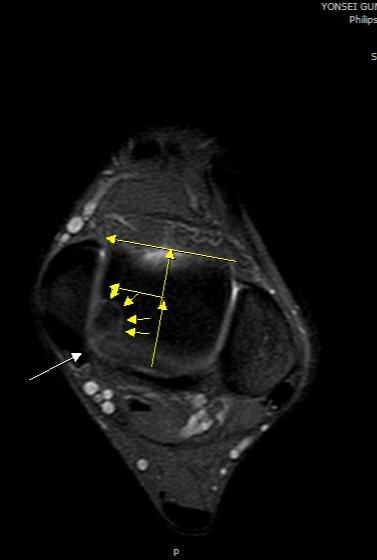

골연골염이 체중 부하 관절면에 몇퍼센트 정도 되어있는건지 판독 부탁드립니다

• 2번 째 사진